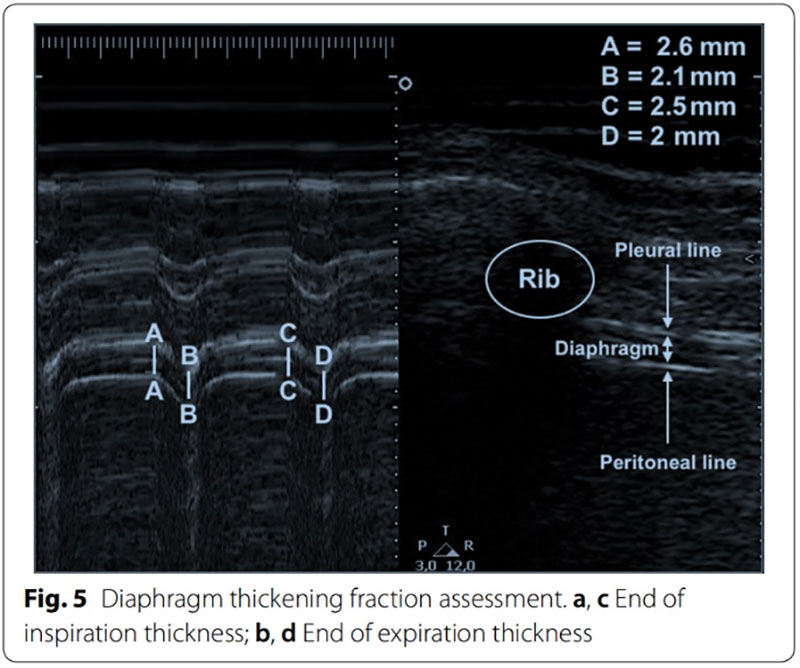

2个膈肌超声指标可指导脱机

b.膈肌增厚分数 (DTF, %):DTF=(平静吸气末膈肌厚度-平静呼气末膈肌厚度)/平静呼气末膈肌厚度×100%